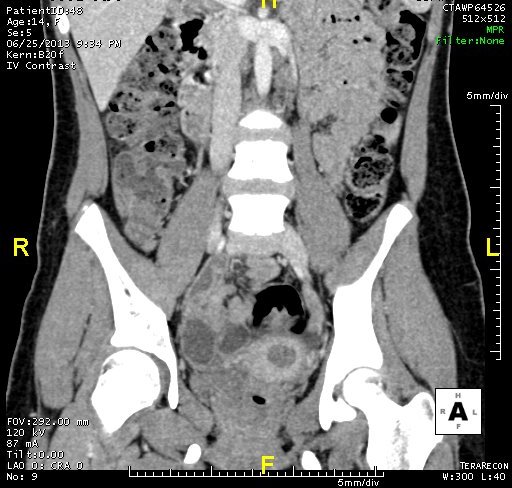

MÀNG TRINH BÍT

Bệnh nhân nữ 14 tuổi. Đau bụng hố chậu (P) 3 ngày, đau liên tục ngày càng tăng.

Tiền sử: Chưa có kinh lần nào.